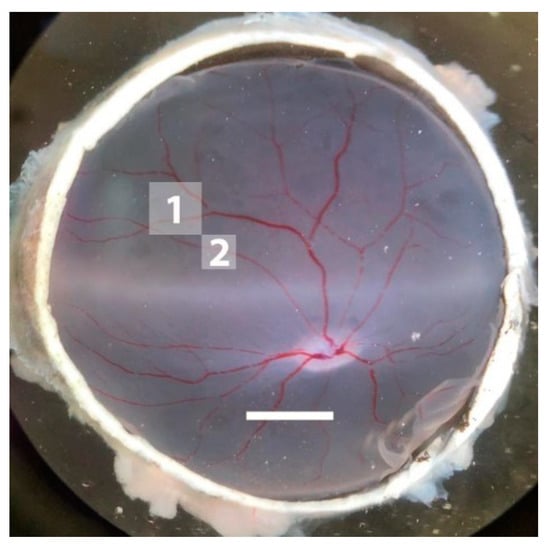

2.1. Effects of I/R on Monitoring Parameters

4.3. Surgical Procedure